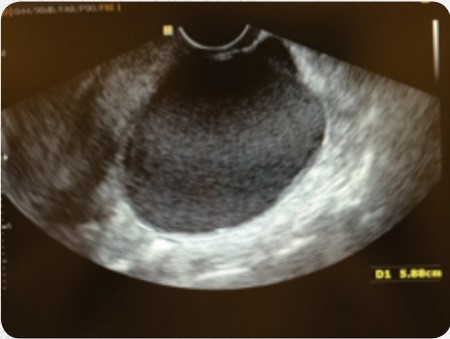

Um implante superficial atinge a face externa dos ovários, provoca uma retração para o interior do mesmo e forma cistos. O tamanho dos cistos é variável e causa alterações da anatomia destes órgãos. O diagnóstico é fácil, feito pelo ultrassom.

O tratamento quase sempre é cirúrgico por videolaparoscopia. O rigor da técnica cirúrgica utilizada é fundamental para que se evite o prejuízo da reserva ovariana, caso contrário, junto com o tecido do cisto, poderá ser retirado também tecido ovariano com óvulos de boa qualidade podendo levar até à falência ovariana precoce. O cisto pode estar associado a endometriose de outros órgãos formando aderências. Muitas vezes a paciente não tem sintomas e o diagnóstico pode ocorrer em um exame ginecológico de rotina. A indicação cirúrgica vai depender do tamanho do cisto entre outras variáveis.